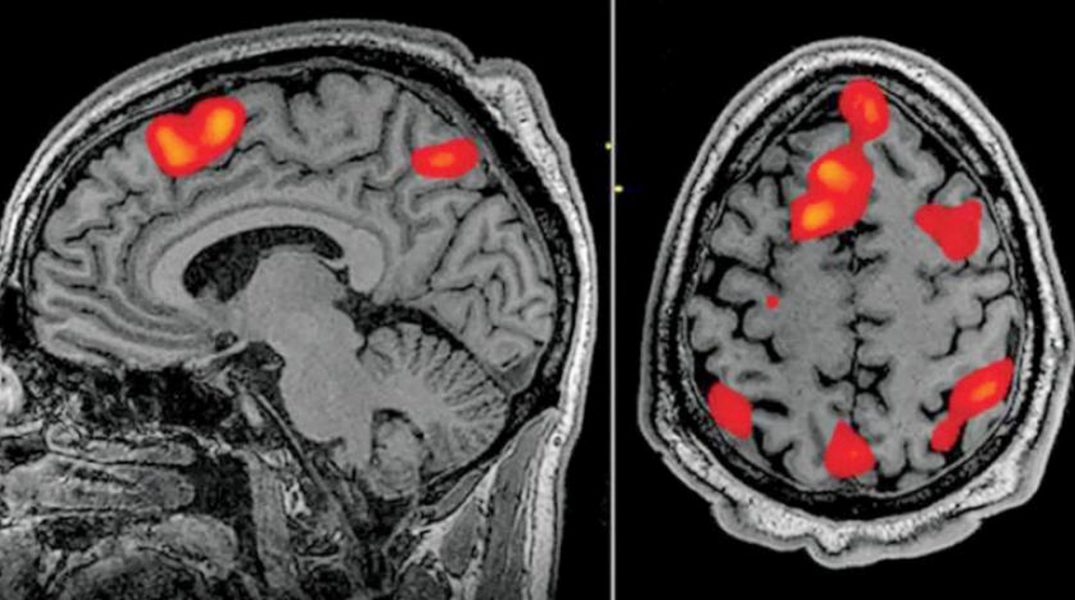

طُوّر جهاز فك ترميز يعتمد على الذكاء الصناعي، قادر على ترجمة نشاط الدماغ إلى نص متدفق باستمرار، في اختراق يتيح قراءة أفكار المرء بطريقة غير جراحية، وذلك للمرة الأولى على الإطلاق، حسب صحيفة «الغارديان» البريطانية.

وبمقدور جهاز فك الترميز إعادة بناء الكلام بمستوى هائل من الدقة، أثناء استماع الأشخاص لقصة ما – أو حتى تخيلها في صمت – وذلك بالاعتماد فقط على مسح البيانات بالتصوير بالرنين المغناطيسي الوظيفي فقط.

وجدير بالذكر أن أنظمة فك ترميز اللغة السابقة استلزمت عمليات زراعة جراحية. ويثير هذا التطور الأخير إمكانية ابتكار سبل جديدة لاستعادة القدرة على الكلام لدى المرضى الذين يجابهون صعوبة بالغة في التواصل، جراء تعرضهم لسكتة دماغية أو مرض العصبون الحركي.

ويذكر أنه من المثير في هذا الإنجاز أنه يتغلب على قيود أساسية مرتبطة بالتصوير بالرنين المغناطيسي الوظيفي، وترتبط بحقيقة أنه بينما يمكن لهذه التكنولوجيا تعيين نشاط الدماغ إلى موقع معين بدقة عالية على نحو مذهل، يبقى هناك تأخير زمني كجزء أصيل من العملية، ما يجعل تتبع النشاط في الوقت الفعلي في حكم المستحيل.

ويقع هذا التأخير لأن فحوصات التصوير بالرنين المغناطيسي الوظيفي تقيس استجابة تدفق الدم لنشاط الدماغ، والتي تبلغ ذروتها وتعود إلى خط الأساس خلال قرابة 10 ثوانٍ، الأمر الذي يعني أنه حتى أقوى جهاز فحص لا يمكنه تقديم أداء أفضل من ذلك.

وتسبب هذا القيد الصعب في إعاقة القدرة على تفسير نشاط الدماغ استجابة للكلام الطبيعي؛ لأنه يقدم «مزيجاً من المعلومات» منتشراً عبر بضع ثوانٍ.

ورغم ذلك، نجحت نماذج اللغة الكبيرة – المقصود هنا نمط الذكاء الصناعي الذي يوجه «تشات جي بي تي» – في طرح سبل جديدة. وتتمتع هذه النماذج بالقدرة على تمثيل المعنى الدلالي للكلمات بالأرقام، الأمر الذي يسمح للعلماء بالنظر في أي من أنماط النشاط العصبي تتوافق مع سلاسل كلمات تحمل معنى معيناً، بدلاً من محاولة قراءة النشاط كلمة بكلمة.